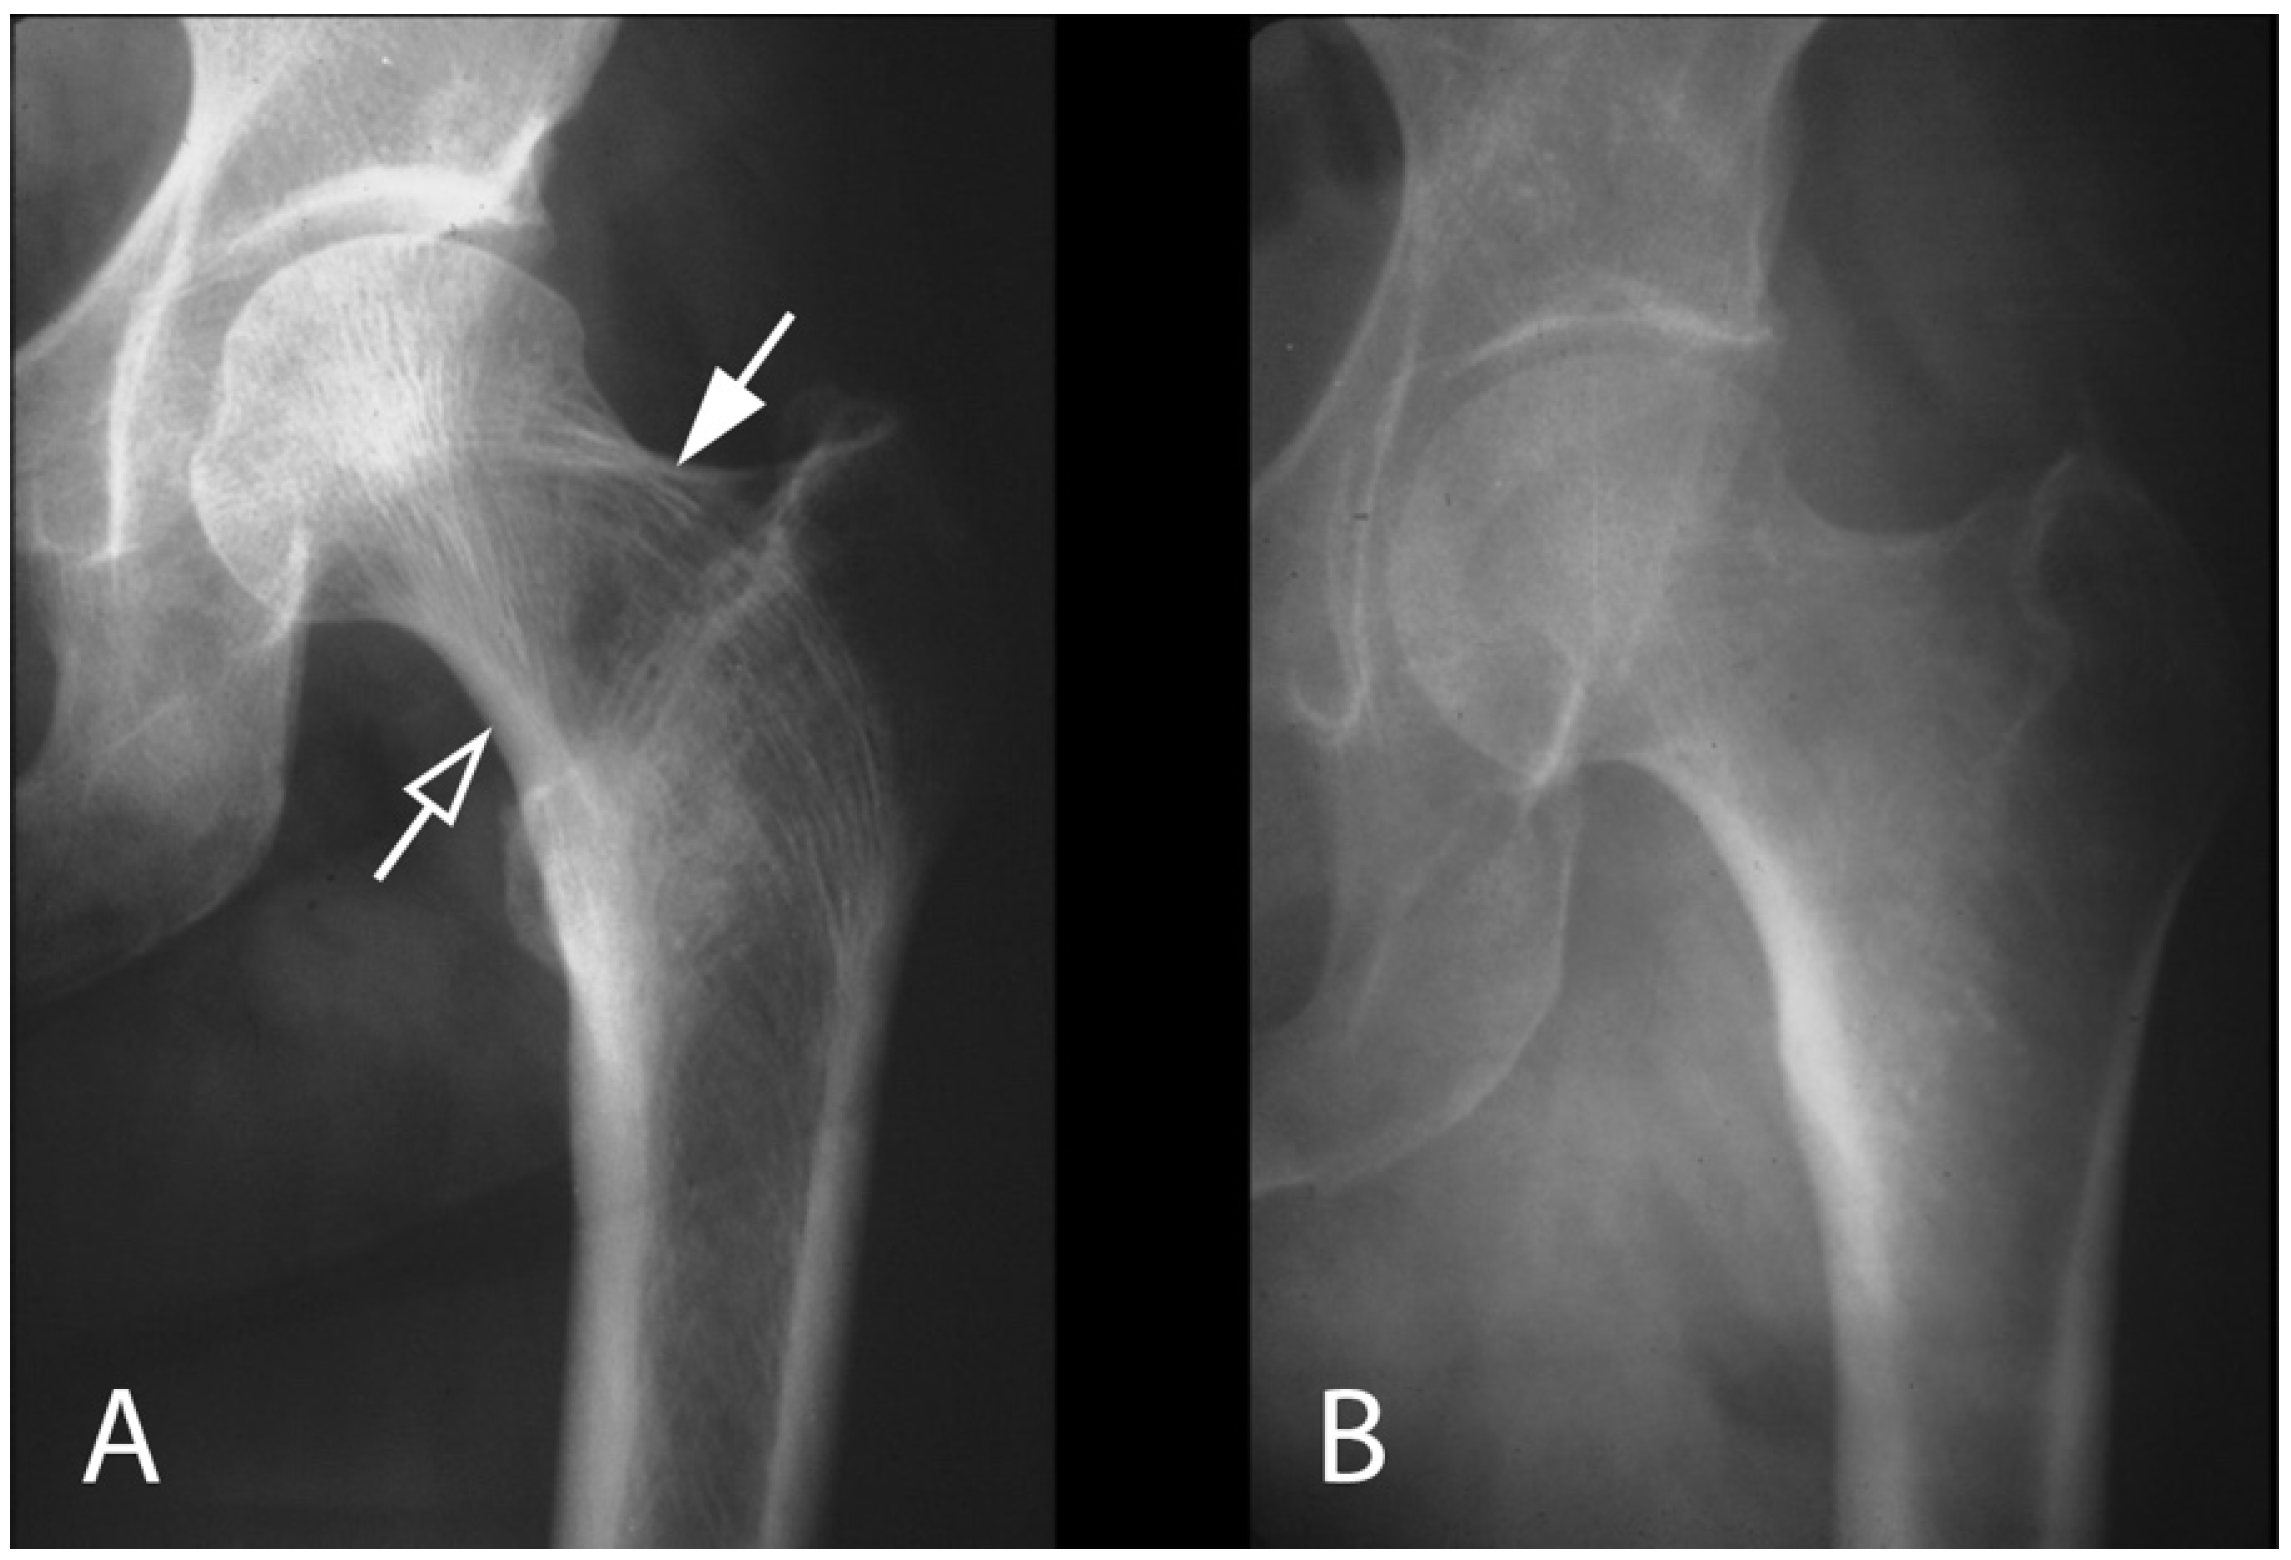

- Zhang, X.; Chen, C.; Duan, H.; Tu, C. Radiographic classification and treatment of fibrous dysplasia of the proximal femur: 227 femurs with a mean follow-up of 6 years. J. Orthop. Surg. Res. 2015, 10, 171. [Google Scholar] [CrossRef]

- Ippolito, E.; Farsetti, P.; Boyce, A.M.; Corsi, A.; De Maio, F.; Collins, M.T. Radiographic classification of coronal plane femoral deformities in polyostotic fibrous dysplasia. Clin. Orthop. Relat. Res. 2014, 472, 1558–1567. [Google Scholar] [CrossRef]